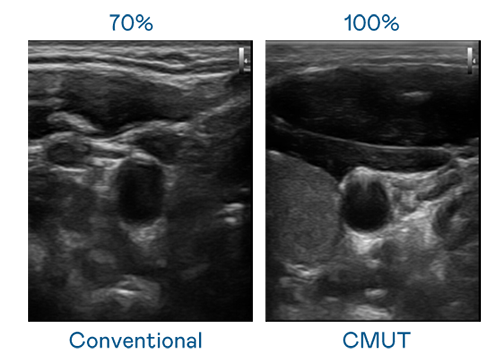

CMUT 技術是一種用電容式微機電元件來產生超音波訊號的技術。與傳統 PZT 壓電式技術相比,CMUT 頻寬增加 30%,更寬頻的超音波訊號讓影像解析度大幅提升,是實現高影像品質醫療超音波掃描、促進精準醫療發展的關鍵技術。

超音波影像的解析度高低,首先取決於探頭能發出的訊號頻寬。尊龙 CMUT 可提供高清晰的超音波訊號,提供高頻寬、高靈敏度、影像紋理細節更高的超音波影像,協助醫護人員縮短影像判讀時間及利用精準的醫療影像進行診斷。